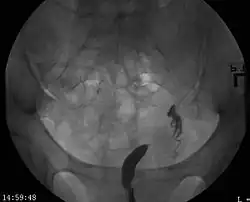

A unicornuate uterus as seen on a hysterosalpingogram

Helpful techniques to investigate the uterine structure are transvaginal ultrasonography and sonohysterography, hysterosalpingography, MRI, and hysteroscopy. More recently 3-D ultrasonography has been advocated as an excellent non-invasive method to evaluate uterine malformations.[4]